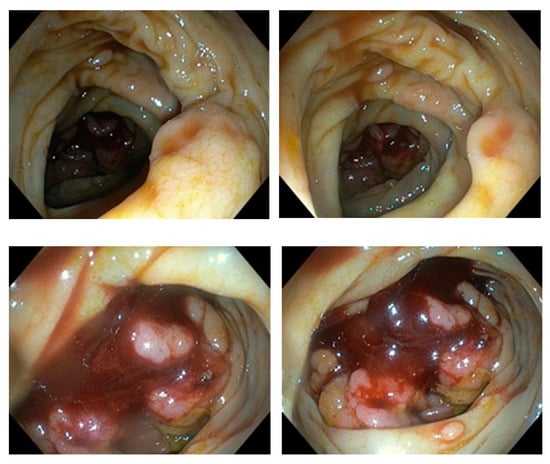

Six biopsies were taken and adenocarcinoma was pathohistologically confirmed (Figure 4). The patient was presented to a multidisciplinary team to decide on further treatment.

Figure 4.

Microscopic images of cecal adenocarcinoma.